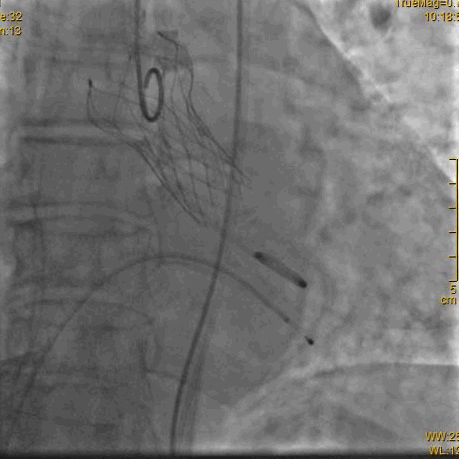

术中操作

球囊预扩确认冠脉风险

瓣膜定位

瓣膜释放过程

瓣膜完全释放后造影,形态良好,无周漏

主动脉重度狭窄行经股动脉的TAVR手术是外科手术禁忌或高危患者的一种手术治疗选择,在多学科协作下,广西国际壮医医院心病科徐先增教授团队完成VitaFlow Liberty™主动脉瓣置换。两个小时紧张有序的操作,术中在第一次瓣膜定位释放移位后,借助VitaFlow Liberty™的电动可回收技术,瓣膜第二次精准定位植入,术后造影检查和心脏彩超评估瓣膜形态活动良好,零压差,无瓣周漏。手术取得圆满成功,患者心功能改善显著。